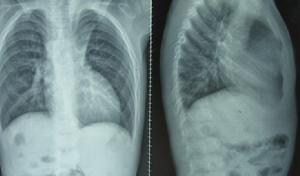

症狀和體徵與巨大的房間隔缺損和房室管畸形相似。常見哭吵時氣急、紫紺。早期出現心力衰竭,逐漸出現紫紺和杵狀指、趾,在肺動脈瓣區有噴射性雜音,第2音亢進固定性分裂,心尖區有二尖瓣關閉不全的收縮期雜音。輔助檢查

(3) 切面切超聲心動圖檢查:左、右心房之間,房間隔回聲反射消失,四腔切面象上正常情況下,由房間隔、室間隔、二尖瓣、三尖瓣形成的十字形回聲反射改變為T字形回聲反射。